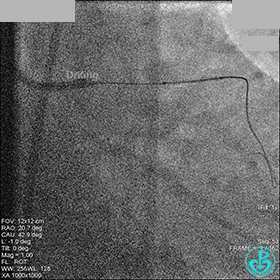

右冠脉中段充分扩张后欲植入3.5×38mm支架时,支架难以通过中远段扭曲处,且指引导管、导丝弹出飞扬。反复尝试导丝重新到达右冠脉远端时通过不顺利,局部造影剂滞留,远端血流接近3级。

右冠脉血流3级,患者无症状,终止手术。

1周后再次上台,右冠脉3级血流,3段局限性严重狭窄,内膜模糊,应该是上次操作夹层遗留下的血肿。